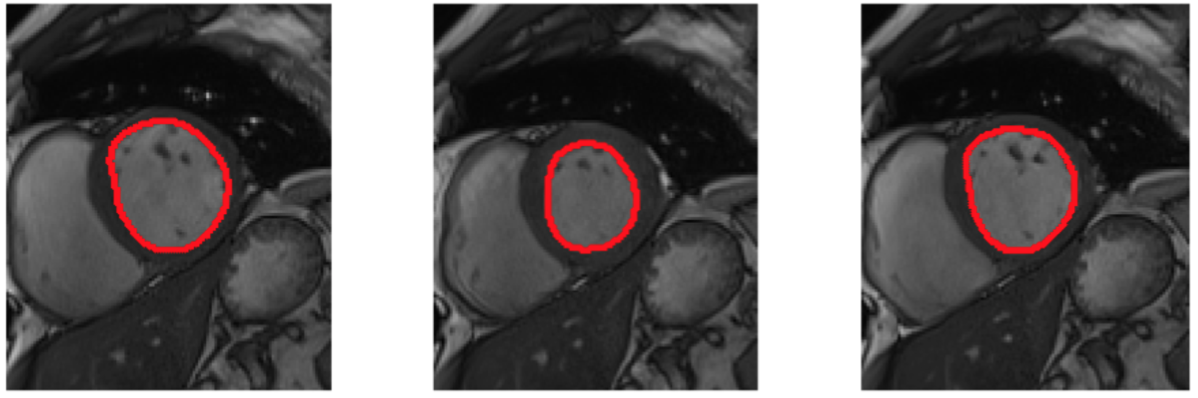

We performed an automatic detection of endocardium volume and its eccentricity based on computer vision algorithm starting from raw MRI short axis frames of a complete cardiac cycle.

In this work we tried to estimate the heart dynamic based on an automatic computer vision algorithm that tries first to extract the location of the left ventriculum (LV) from chest MRI acquisition performing a region of interest (ROI) identification on the first frame, applying then the mask extracted to the subsequent frames in order to save computation speed. The automatic coordinate detecion of the LV is achieved by applying a circular Hough Trasform, the purpose of the technique is to find imperfect instances of objects within a certain class of shapes by a voting procedure. In this application we set the equation of a circle as the default recognition shape, the radius range wa set between 15-30 pixels which correspond to a 27-45 mm that correspond to anatomical range size of the LV.

After extracting the correct circle location a binary mask is created and then convoluted with all the frames in order to perform the next post processing steps just on the ROI

Then, to perform a correct segmentation of the object, after applying a selection criteria based on a simple binary threshold on the pixel intensity since the structure of interest present higher values then the background, starting from the binarized image extracted, the boundaries of the object are extracted based on pixel connectivity criteria.

To estimate the volume we multiplied the number of pixel for the axial resolution contained in the metadata of the MRI aquisition, the eccentricity is calculated as the ratio of the distances of a point on the ellipse from the focus, and the directrix.